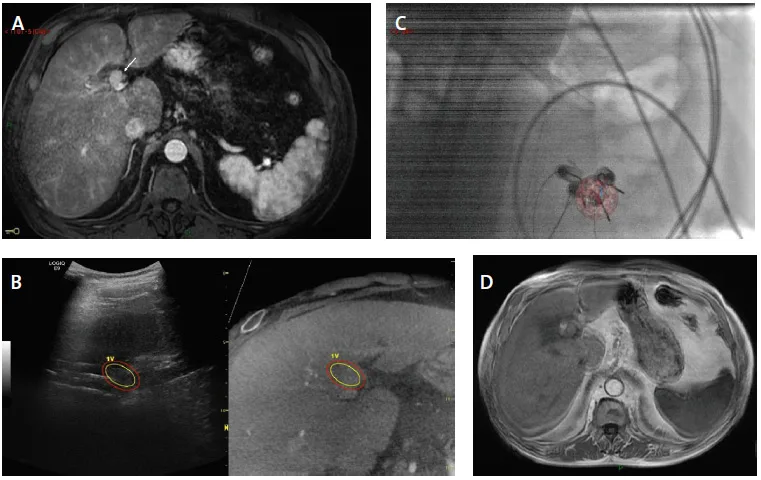

Figure 5. Ablation par electroporation irréversible par guidage multimodale fusionné d’un CHC nodulaire de 2 cm à développement préhilaire.

A. IRM axiale au temps artériel de l’injection intraveineuse de gadolinium montrant une tumeur nodule hypervasculaire du segment 4 (flèche) venant en contact de la voie biliaire principale

B. Synchronisation de l’acquisition 3D RX cone beam CT pré ablative avec l’échographie permettant de renforcer la visualisation échographique de la tumeur en propageant un contourage 3D de la tumeur réalisé à partir des images cone beam CT synchronisées.

C. Visualisation en fluoroscopie de l’agencement de quatre électrodes par rapport à la superposition de l’image segmentée de la tumeur à partir des coupes cone beam CT. Noter la visualisation bull eyes des quatre électrodes implantées en périphérie du nodule, permise par la rotation de l’arceau.

D. L’IRM de contrôle un mois après, au temps artériel de l’injection intraveineuse de produit de contraste gadoliné montre un centrage parfait de la zone d’ablation par rapport au nodule qui présente un aspect de réponse complète comme en atteste la disparition de la prise de contraste.